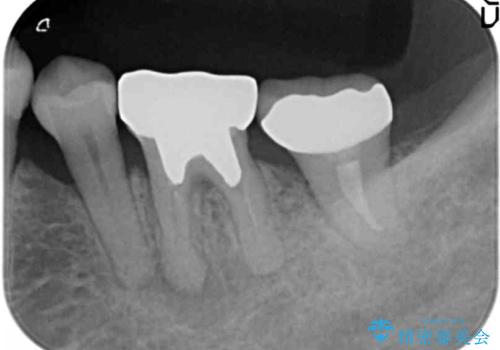

移植後、生着を待って根管治療及び補綴修復を行いました。

親知らずの移植により、自分の歯を用いて咬合機能を回復することができ、大変喜んで頂けました。

被せ物の種類:オールセラミッククラウン スタンダード